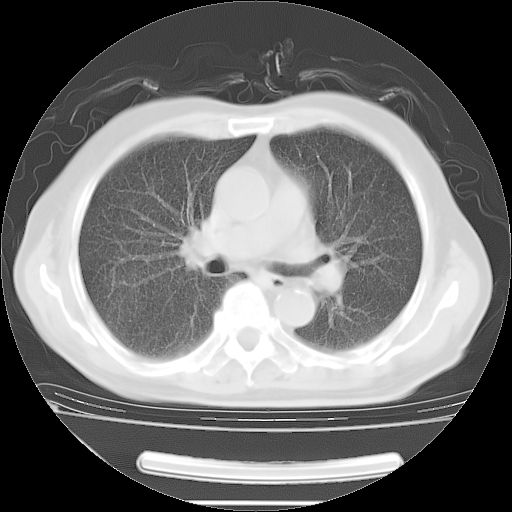

今天复查肺部CT,发现双肺广泛磨玻璃样改变。所以我把3月19日和5月9日相隔50天的肺部CT上传。请大家会诊。

2009年3月19日肺部CT片。

2009年3月19日肺部CT

大致读了系列胸部CT:纵隔窗无明显异常,肺窗:从4、27至今:主要是双肺中下野外带可见毛玻璃样改变,目前处于急性肺泡炎阶段,至于原因考虑1、结替组织或胶原血管性疾病所致?2、恶性疾病如恶组在肺部所致的表现或细支气管肺泡癌?3、药物或其它原因如肺蛋白沉着症所致肺泡炎目前不太可能?总之,明天就去请我院的呼吸科、感染科、血液科和临免专家会诊哈。